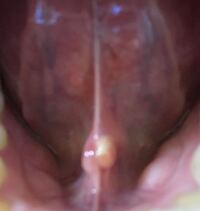

舌の裏に二股に分かれたデキモノがあります (歯科相談室) 舌乳頭腫、舌繊維腫とは、舌にできる「おでき」「いぼ」のようなもので、比較的よく見られる良性の腫瘍です。 機械的刺激が原因で起こることが多いため、刺激を与えている原因の除去や舌のできもの|歯チャンネル歯科相談室 22 写真あり 舌の側面の出来物が痛い 23 写真あり 舌の右側横にできた白いものが癌ではないかと心配 24 妊娠中、舌の小さなしこりと白い出来物が心配になってきました 「ノドに白いものがある」とのことで患者さんが来られました。 ノドを診てみると↓ 左の扁桃に白いものが これは何かと言いますと 「膿栓(のうせん)」 です 「膿栓」について説明する前に、 「扁桃(へんとう)」について説明したいと思います。

口の中の白いできもの 熊本 くまモンファン 耳鼻咽喉科医の みみ はな のど あれこれ